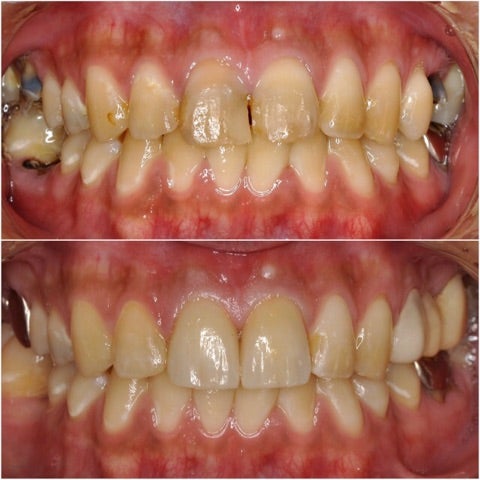

本日は歯科恐怖症の為、奥歯の虫歯を放置してしまい、だんだんと前歯も欠けて日に日に見栄えが悪くなって来た…

▶︎患者様は「最近どんどん歯がボロボロになってきている」と仰っていました。

一見歯の状態はそこまでボロボロには見えませんが、実は奥歯の状態が特に悪く、痛みもあり食事はほぼ前歯を使用している状態です。

その結果前歯へのダメージが蓄積し、着色や欠けが目立つようになってきてしまっています。

診査診断後、患者様と十分にカウンセリングを行い、無痛治療での全顎的治療を開始しました。

奥歯は重度の虫歯で抜歯をしなければいけない部位があり、目立たない部位には健康保険を使用し、銀歯での処置をしています。

ダメージの大きい前歯(一番前の2本)に対しては、周りの歯の色に特徴があることからジルコニアセラミッククラウン・プレミアム ¥220,000-/本

を使用し、歯科技工士立会いの下、周りの歯と調和するように治療、作成を行いました。